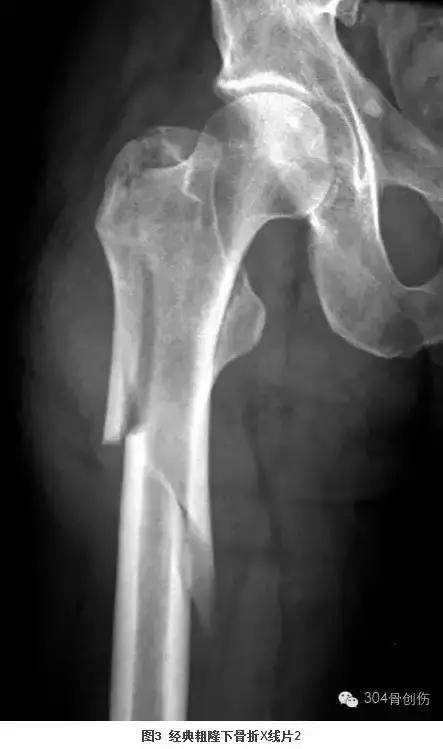

抗骨折疏松的药物为何导致不典型股骨骨折?与骨自身修复重建和股骨结构有关。双膦酸盐通过抑制破骨细胞皱褶缘的形成,阻止破骨细胞分泌氢离子与溶酶体酶进入Howship腔隙,从而抑制破骨细胞介导的骨吸收过程,也意味着骨重建的减少。这可导致一系列骨材料特性的变化:胶原交联异常,胶原成熟度下降,微损伤积聚(图4、5)。使骨的屈服强度下降,脆性增加,易出现疲劳骨折。而骨强度不仅由骨材料特性决定,同时受骨结构特性影响。股骨近端的解剖形态决定了股骨外侧皮质为其张力侧,承受较大的应力(图6、7),亚洲人群,非典型股骨骨折患者股骨的前外侧弧度更为显著,且下肢解剖轴和机械轴之间的偏移与骨折部位高度相关,股骨弧度过大可导致牵张应力集中于股骨前外侧面,造成非典型股骨骨折,类似道理见于折断的铅笔和被风刮断的树枝(图8、9)。